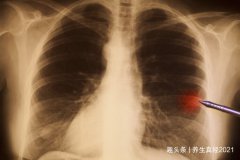

近日,江苏杨女士体检发现肺部出现5mm小阴影,由于结节太小无法辨认良恶性质,医生建议定期复查。然而,李女士却把这个结节当成了定时炸弹,为此忧心忡忡、没有胃口,一个月就